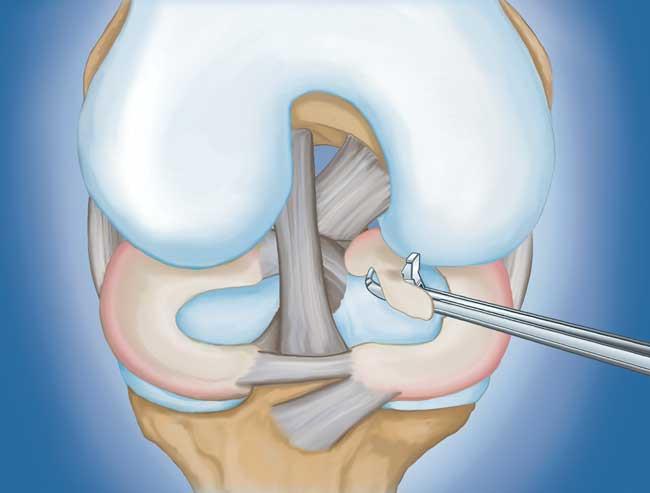

程序。  膝關(guān)節(jié)鏡檢查是最常進(jìn)行的外科手術(shù)之一。在這個(gè)過(guò)程中,外科醫(yī)生通過(guò)膝蓋上的一個(gè)小切口(入口)插入一個(gè)微型相機(jī)。這提供了膝蓋內(nèi)部的清晰視圖。然后外科醫(yī)生通過(guò)兩個(gè)或三個(gè)其他小入口插入手術(shù)器械以修剪或修復(fù)撕裂。

• 部分半月板切除術(shù)。  在這個(gè)過(guò)程中,受損的半月板組織被修剪掉。該程序通常允許在手術(shù)后立即負(fù)重和全方位運(yùn)動(dòng)。

• 半月板修復(fù)。  一些半月板撕裂可以通過(guò)將撕裂的碎片縫合(縫合)在一起來(lái)修復(fù)。撕裂能否成功修復(fù)取決于撕裂的類型,以及受傷半月板的整體狀況。因?yàn)榘朐掳灞仨氁黄鹩?,修?fù)的恢復(fù)時(shí)間比半月板切除術(shù)長(zhǎng)。

部分半月板切除術(shù)特寫

用縫線修復(fù)撕裂的半月板